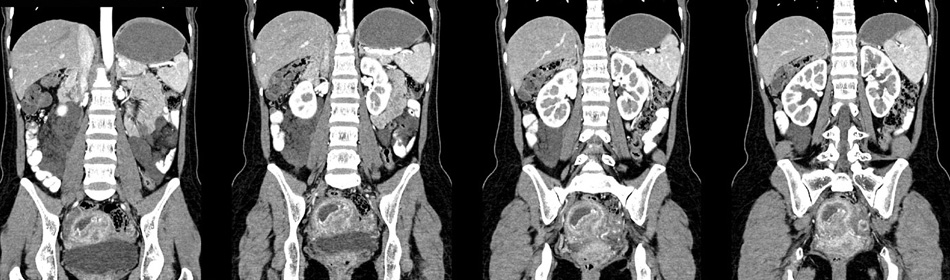

女性,28岁,停经3月,腹部膨隆1月,产前检查发现腹部占位

{肿块中心ct值27hu,增强后,动脉期、门脉期均无明显强化)

患者手术病理:腹腔囊性淋巴管瘤,象这样充满整个腹腔的的确很少见